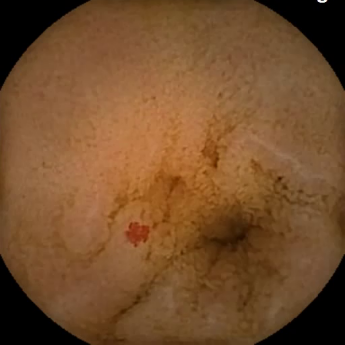

(a) I: None -

R: Angiectasia

Figure 5: Representative VCE images, that were identified as mislabeled by our pipeline and re-annotated by clinical experts (I: Initial, R: Revised).

Furthermore, Figure 5 displays four representative VCE images identified by our proposed approach as mislabeled data, which were subsequently confirmed as incorrectly labeled by the scientific panel and re-annotated accordingly. The first two images were originally annotated as healthy mucosa, but have been corrected to angiectasia (Figure 5a) and polyp (Figure 5b). The second two frames were originally labeled as blood (Figure 5c) and polyp (Figure 5d), but were identified as normal samples by our pipeline and then relabeled respectively. This indicates the effectiveness of our pipeline in detecting present mislabeled data in medical datasets.